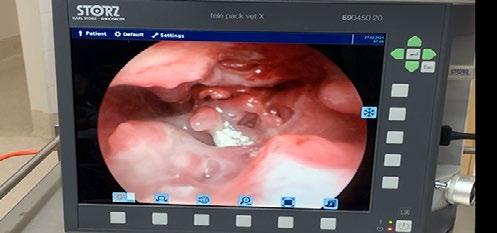

At the re-check, the owner reported no clinical response to the treatment trial so GA and rhinoscopy were planned as we are lucky enough to have a video endoscope at our clinic. Winnie was pre-medicated with methadone (0.3mg/kg) and medetomidine (0.005mg/ kg) intramuscularly. An intravenous catheter was placed, and anaesthetic was induced with 10 mg alfaxalone slowly intravenously to effect. A cuffed endotracheal tube was placed, and anaesthetic was maintained on isoflurane in 100% oxygen.

The most rostral aspect of the left nostril was ulcerated, and inflamed with purulent mucoid discharge which was difficult to direct the scope through. Once past it, there was extensive destruction of the nasal turbinates with a prominent fungal plaque (see Figure 1 and video). The right nostril was mildly inflamed; however, no plaques or destruction of turbinates was observed. We removed the plaque from the left nostril with forceps and placed it in a sterile container. There was also some tissue removed at the same time, half of which we placed in the sterile jar and half we placed in buffered neutral formalin on the off chance that if the culture of the plaque was

non-diagnostic, we could use the fixed sample to look for the presence of fungal hyphae, which, if present, can be seen on histopathology especially with special stains like PAS or Gomori silver.